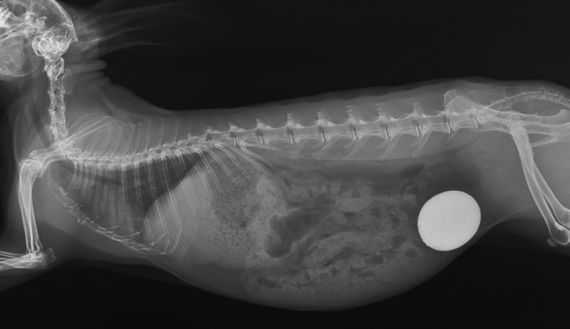

- Weichteilchirurgie (Kastrationen männlich/weiblich, Tumoroperationen, Entfernung von Blasensteinen, Operationen bei Darmverschlüssen und Orthopädie)

- bildgebende Diagnostik (Röntgen, Sonographie, CT-Untersuchungen)